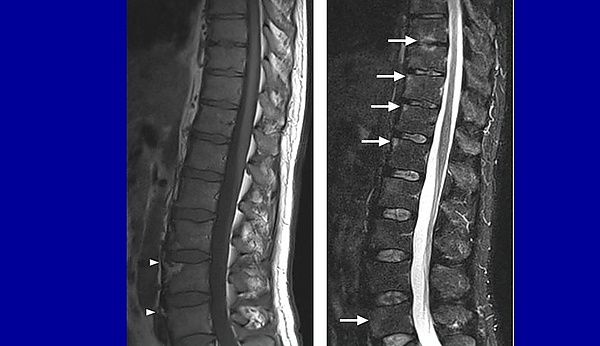

Диагностическая визуализация

Магнитно-резонансная томография (МРТ) — один из лучших методов диагностики при спондилодисците. МРТ демонстрирует высокую чувствительность и специфичность при выявлении спондилодисцита: заболевание диагностируется более чем в 90 % случаев[1]. Компьютерную томографию используют в качестве альтернативы при наличии противопоказаний к МРТ (кардиостимуляторы, несовместимые с МРТ, и другие факторы, связанные с пациентом)[5].